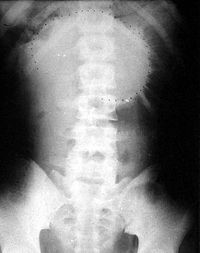

X线检查:一般在肠梗阻发生4-6小时,X线检查及显示出肠腔内气体;立位片或侧位透视或拍片,可见多数液平面及气胀肠袢。但如果没有这些表现,也不能就此排除肠梗阻的可能。